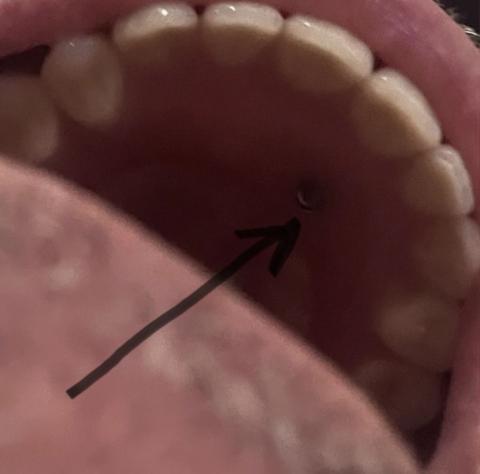

This intra-oral image shows the upper arch with a visible small metallic component located on the palatal side, indicated by an arrow. The appearance is consistent with a denture or implant-retained prosthesis attachment, such as a screw head or retention component, that may be exposed, loosened, or improperly seated.

Small metallic component visible on the palate

Located beneath a removable or fixed prosthesis

Surrounding soft tissue appears mildly irritated

Finding is suggestive of a loose denture screw or exposed attachment

Exposure may indicate prosthesis movement or incomplete seating

Prosthetic attachment exposure

Possible loosening of denture or implant screw

Soft-tissue irritation secondary to hardware contact